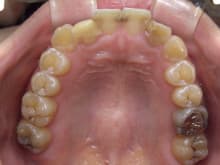

治療前の状態です。

正面写真の向かって右側の側切歯(実際は左側になります。)は歯が折れています。

中央の2本には大きな虫歯があり

向かって左側の歯は2次虫歯になっています。